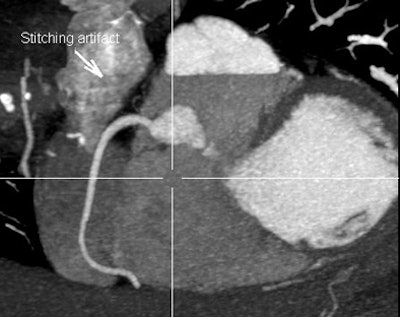

![]() |

| Owing to the need to acquire cardiac images over several heartbeats, coronary CT angiography at 64-detector-row CT produces more artifacts than 320-detector-row CT, which acquires the entire cardiac volume in a single beat, or two beats for a longer triple-rule-out study. Above, 320 image acquired over two heartbeats has a single stitching artifact (arrow), while the 64 image below contains four important artifacts, only one of which is labeled with an arrow. Can you find the rest? Images courtesy of Dr. Melissa Daubert and Dr. Michael Poon. |